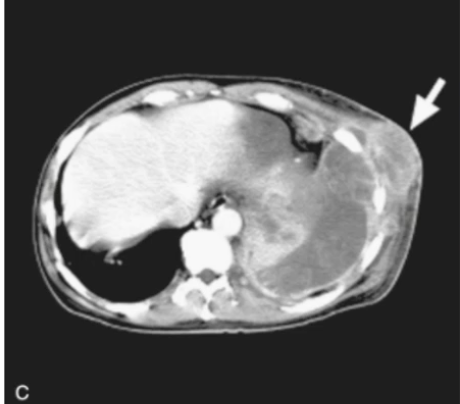

Nocardia - Branching gram positive rod (aerobic)